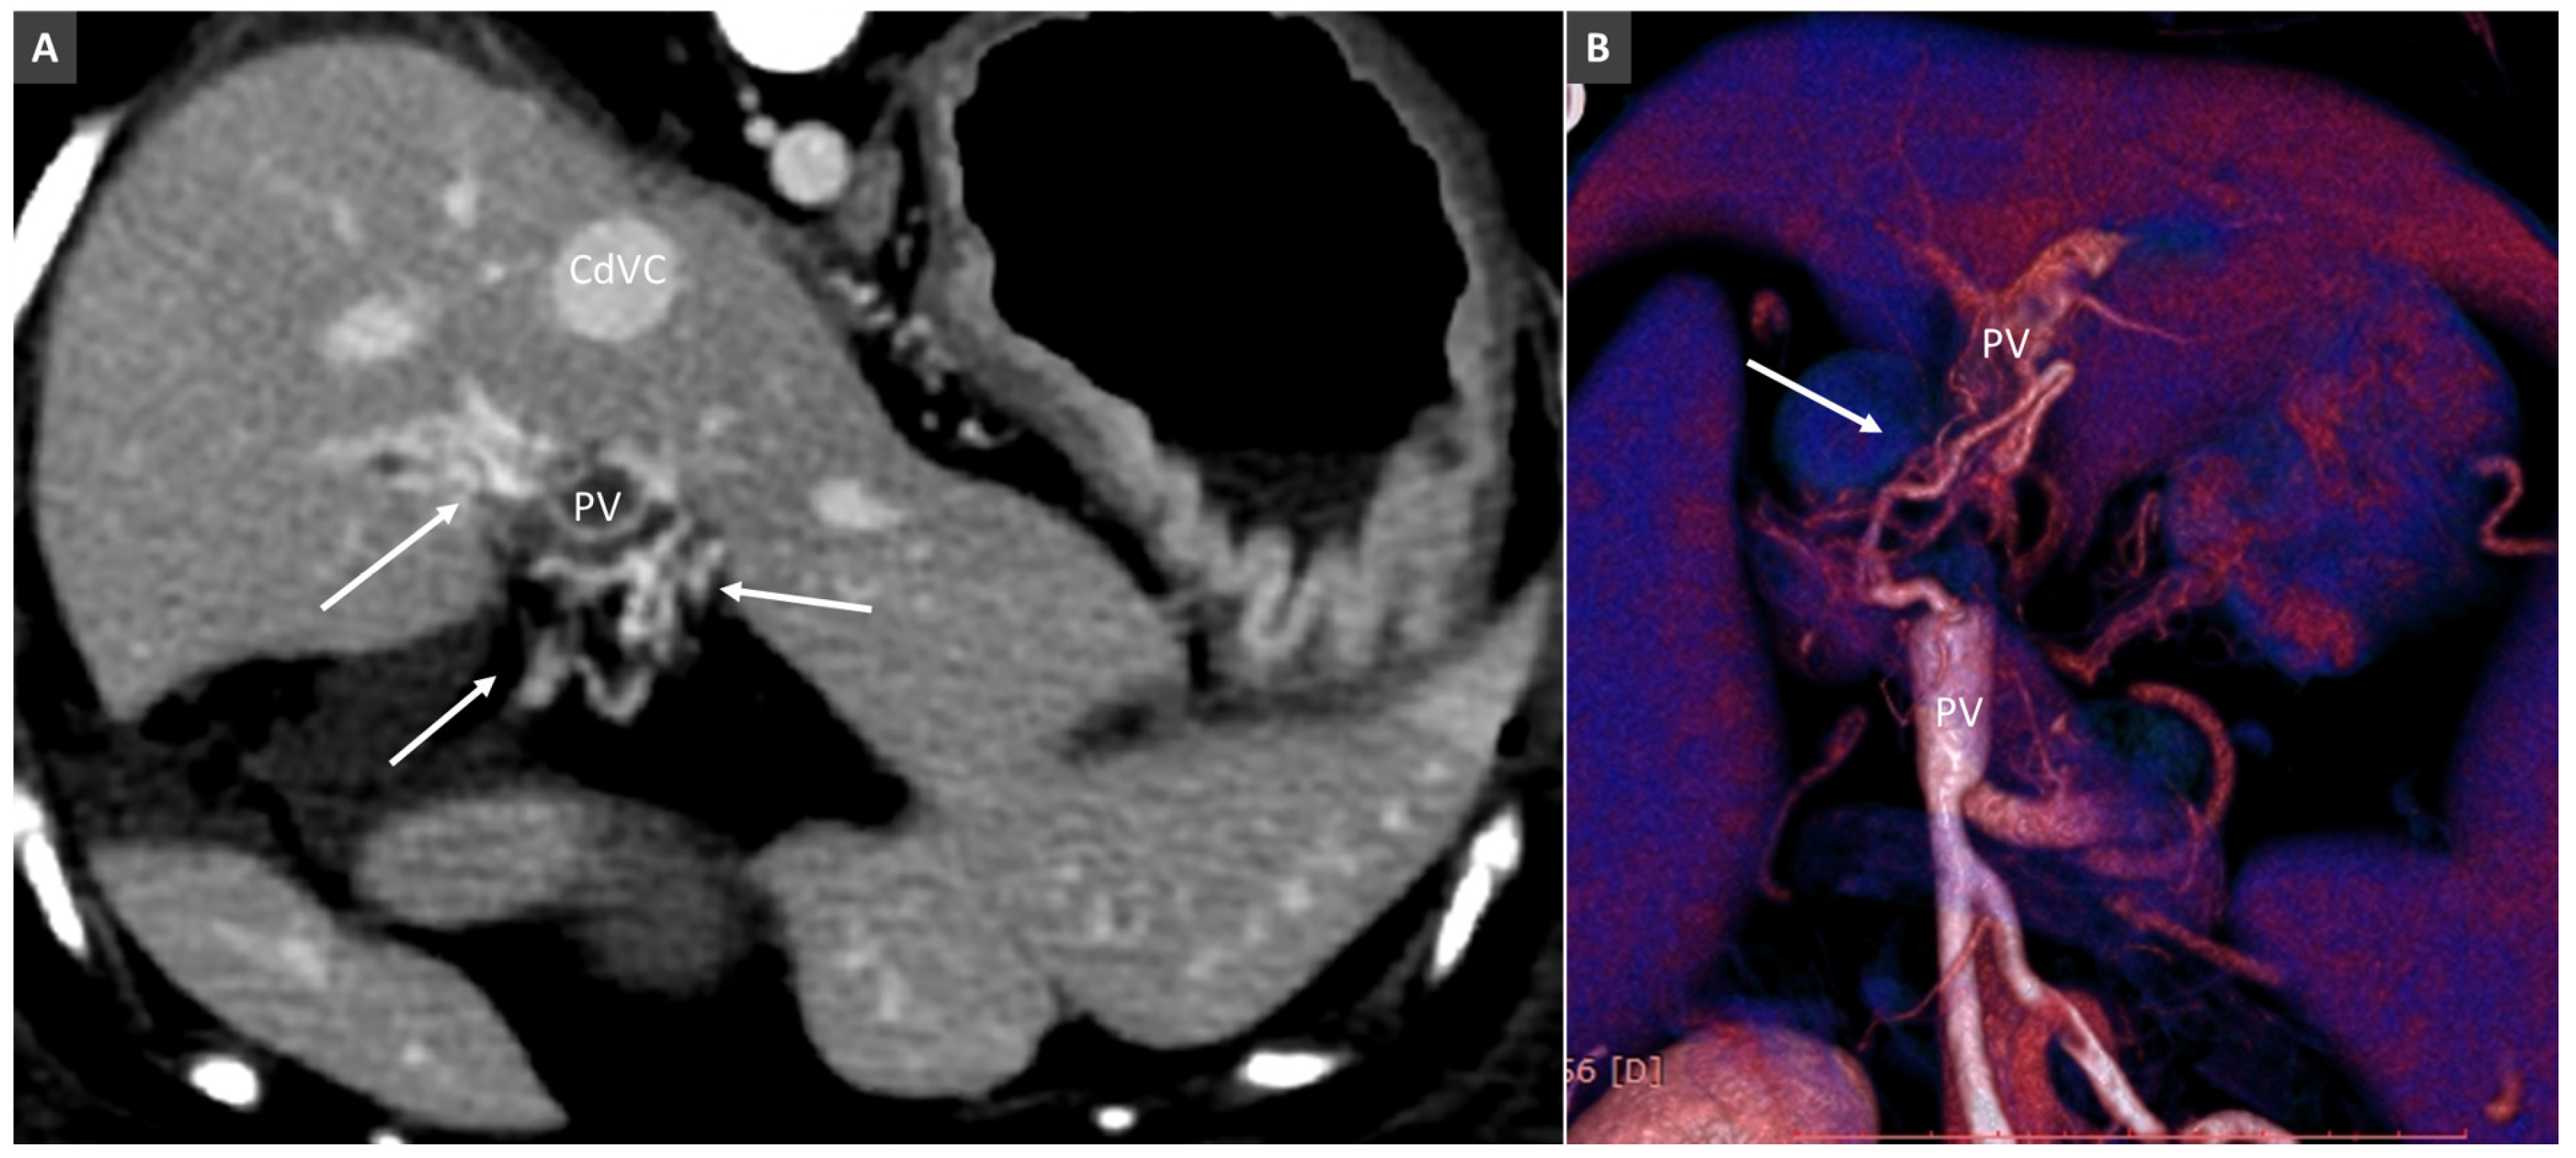

3.8. Porto-Portal Collaterals or Cavernous Transformation of the Portal Vein